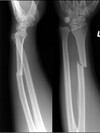

Q

What pathology is shown here?